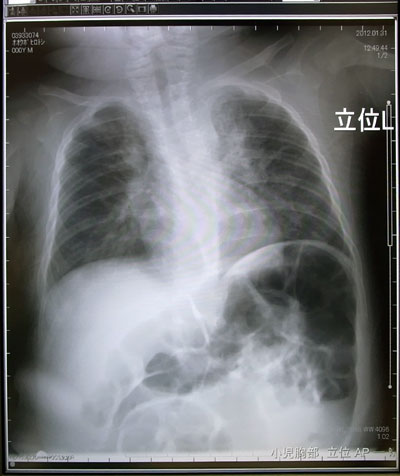

やはり肺炎だった。

![]() |

酸素を止めると血中酸素濃度が下がってしまう。

酸素を外しても酸素濃度が下がらないこと、

飲めるようになること。

それらを確認しての退院になる。

2週間程度と考えておいて欲しい。

との事であった。